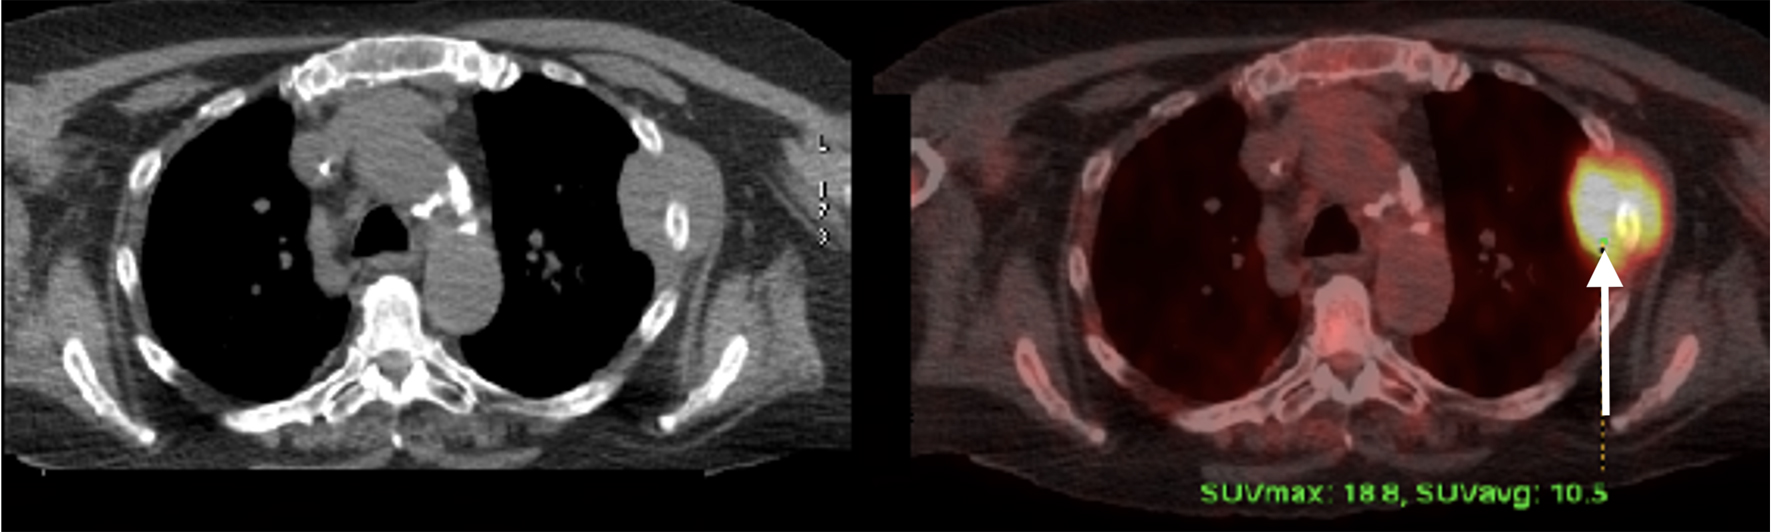

PET scan was repeated in January 2018 and showed interval development of several new FDG avid osseous lesions in the axial and appendicular skeleton as well as an incidentally detected intense hypodense lesion inferiorly in the posterior aspect of the right hepatic lobe with another small, but FDG avid focus more superiorly and medially in the posterior aspect of the right hepatic lobe. She was subsequently referred to an academic hospital by her primary oncologist due to progression of disease on PET (Figs. 1-3). Percutaneous biopsy of this newly identified liver lesion was performed from hepatic segment 6 and the pathology showed numerous abnormal plasmacytoid cells consistent with MM (Figs. 4 and 5). Interestingly, the patient did not have any symptoms or evidence of hepatomegaly on examination. Her liver function tests remained normal at the time of detection of the liver plasmacytoma and for the remainder of her disease course.

![]() Click for large image | Figure 3. Positron emission tomography scan at the time of relapse showing liver involvement. |